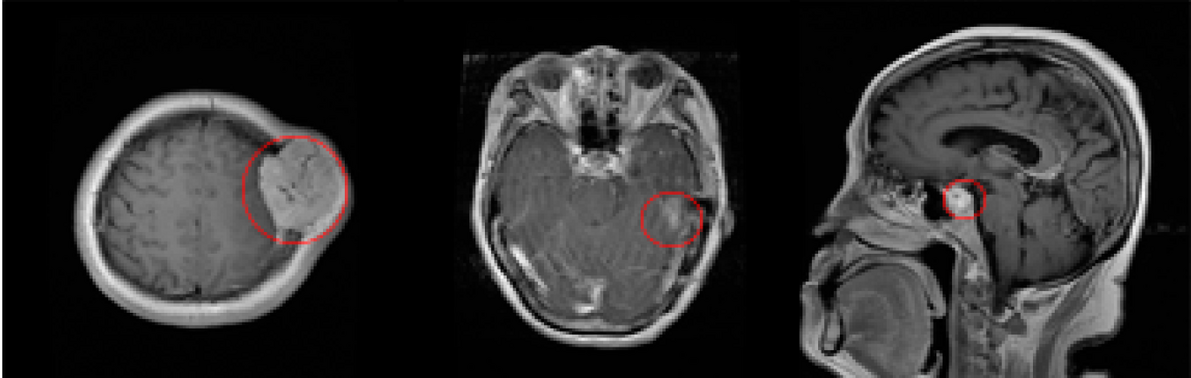

Developed a generative AI model to synthesize brain cancer MRI images for dataset augmentation, enhancing training diversity and improving tumor detection model accuracy.